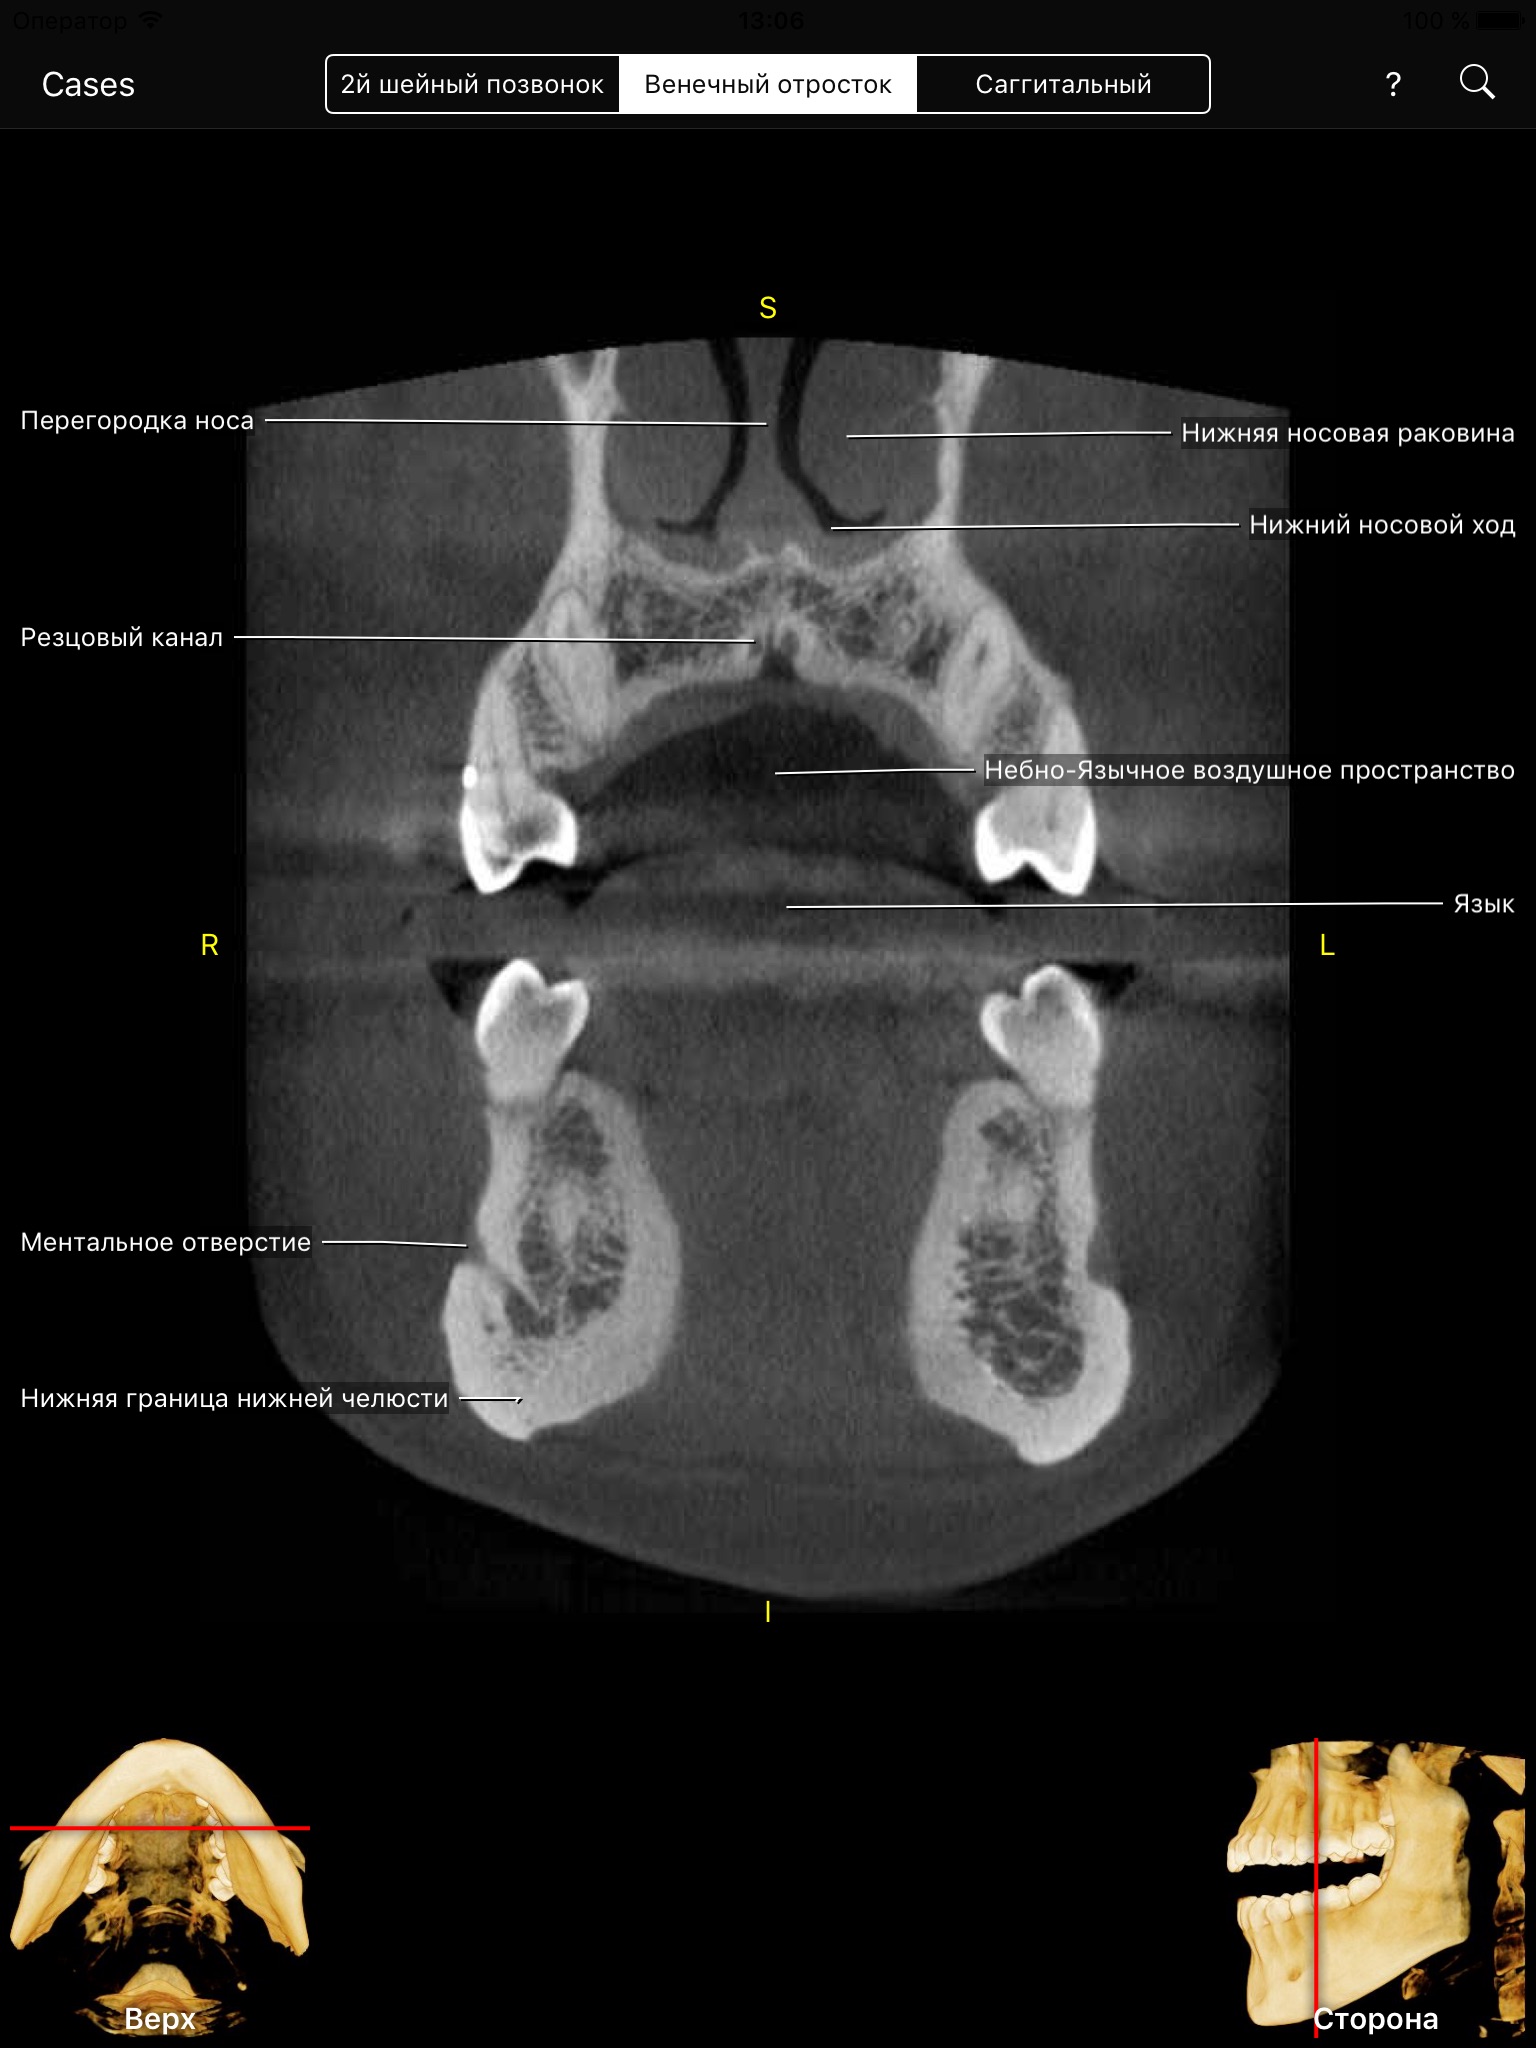

Cone Beam CT has revolutionized diagnosis and treatment planning. Clinicians can use a Cone Beam CT volume to view patient’s head in 3 dimensions using multi-planar reformatted views (MPR), known as: axial, coronal, and sagittal. The volumetric data set has no magnification and no superimposition.

CBCT app allows clinicians, residents, and dental students to learn anatomical landmarks as if they were looking at a CBCT data set through the CBCT viewing software but with all the landmarks visible and animated through all MPR views.

The level of interactivity and visualization is unprecedented. This amazing app covers hundreds of anatomical landmarks visible on CBCT data sets from small to medium to large field of views (FOVs). It also allows you to test your knowledge through the quiz mode, which is very cool. You can also search for a landmark or pick it up from an alphabetical list and the app fly you there.